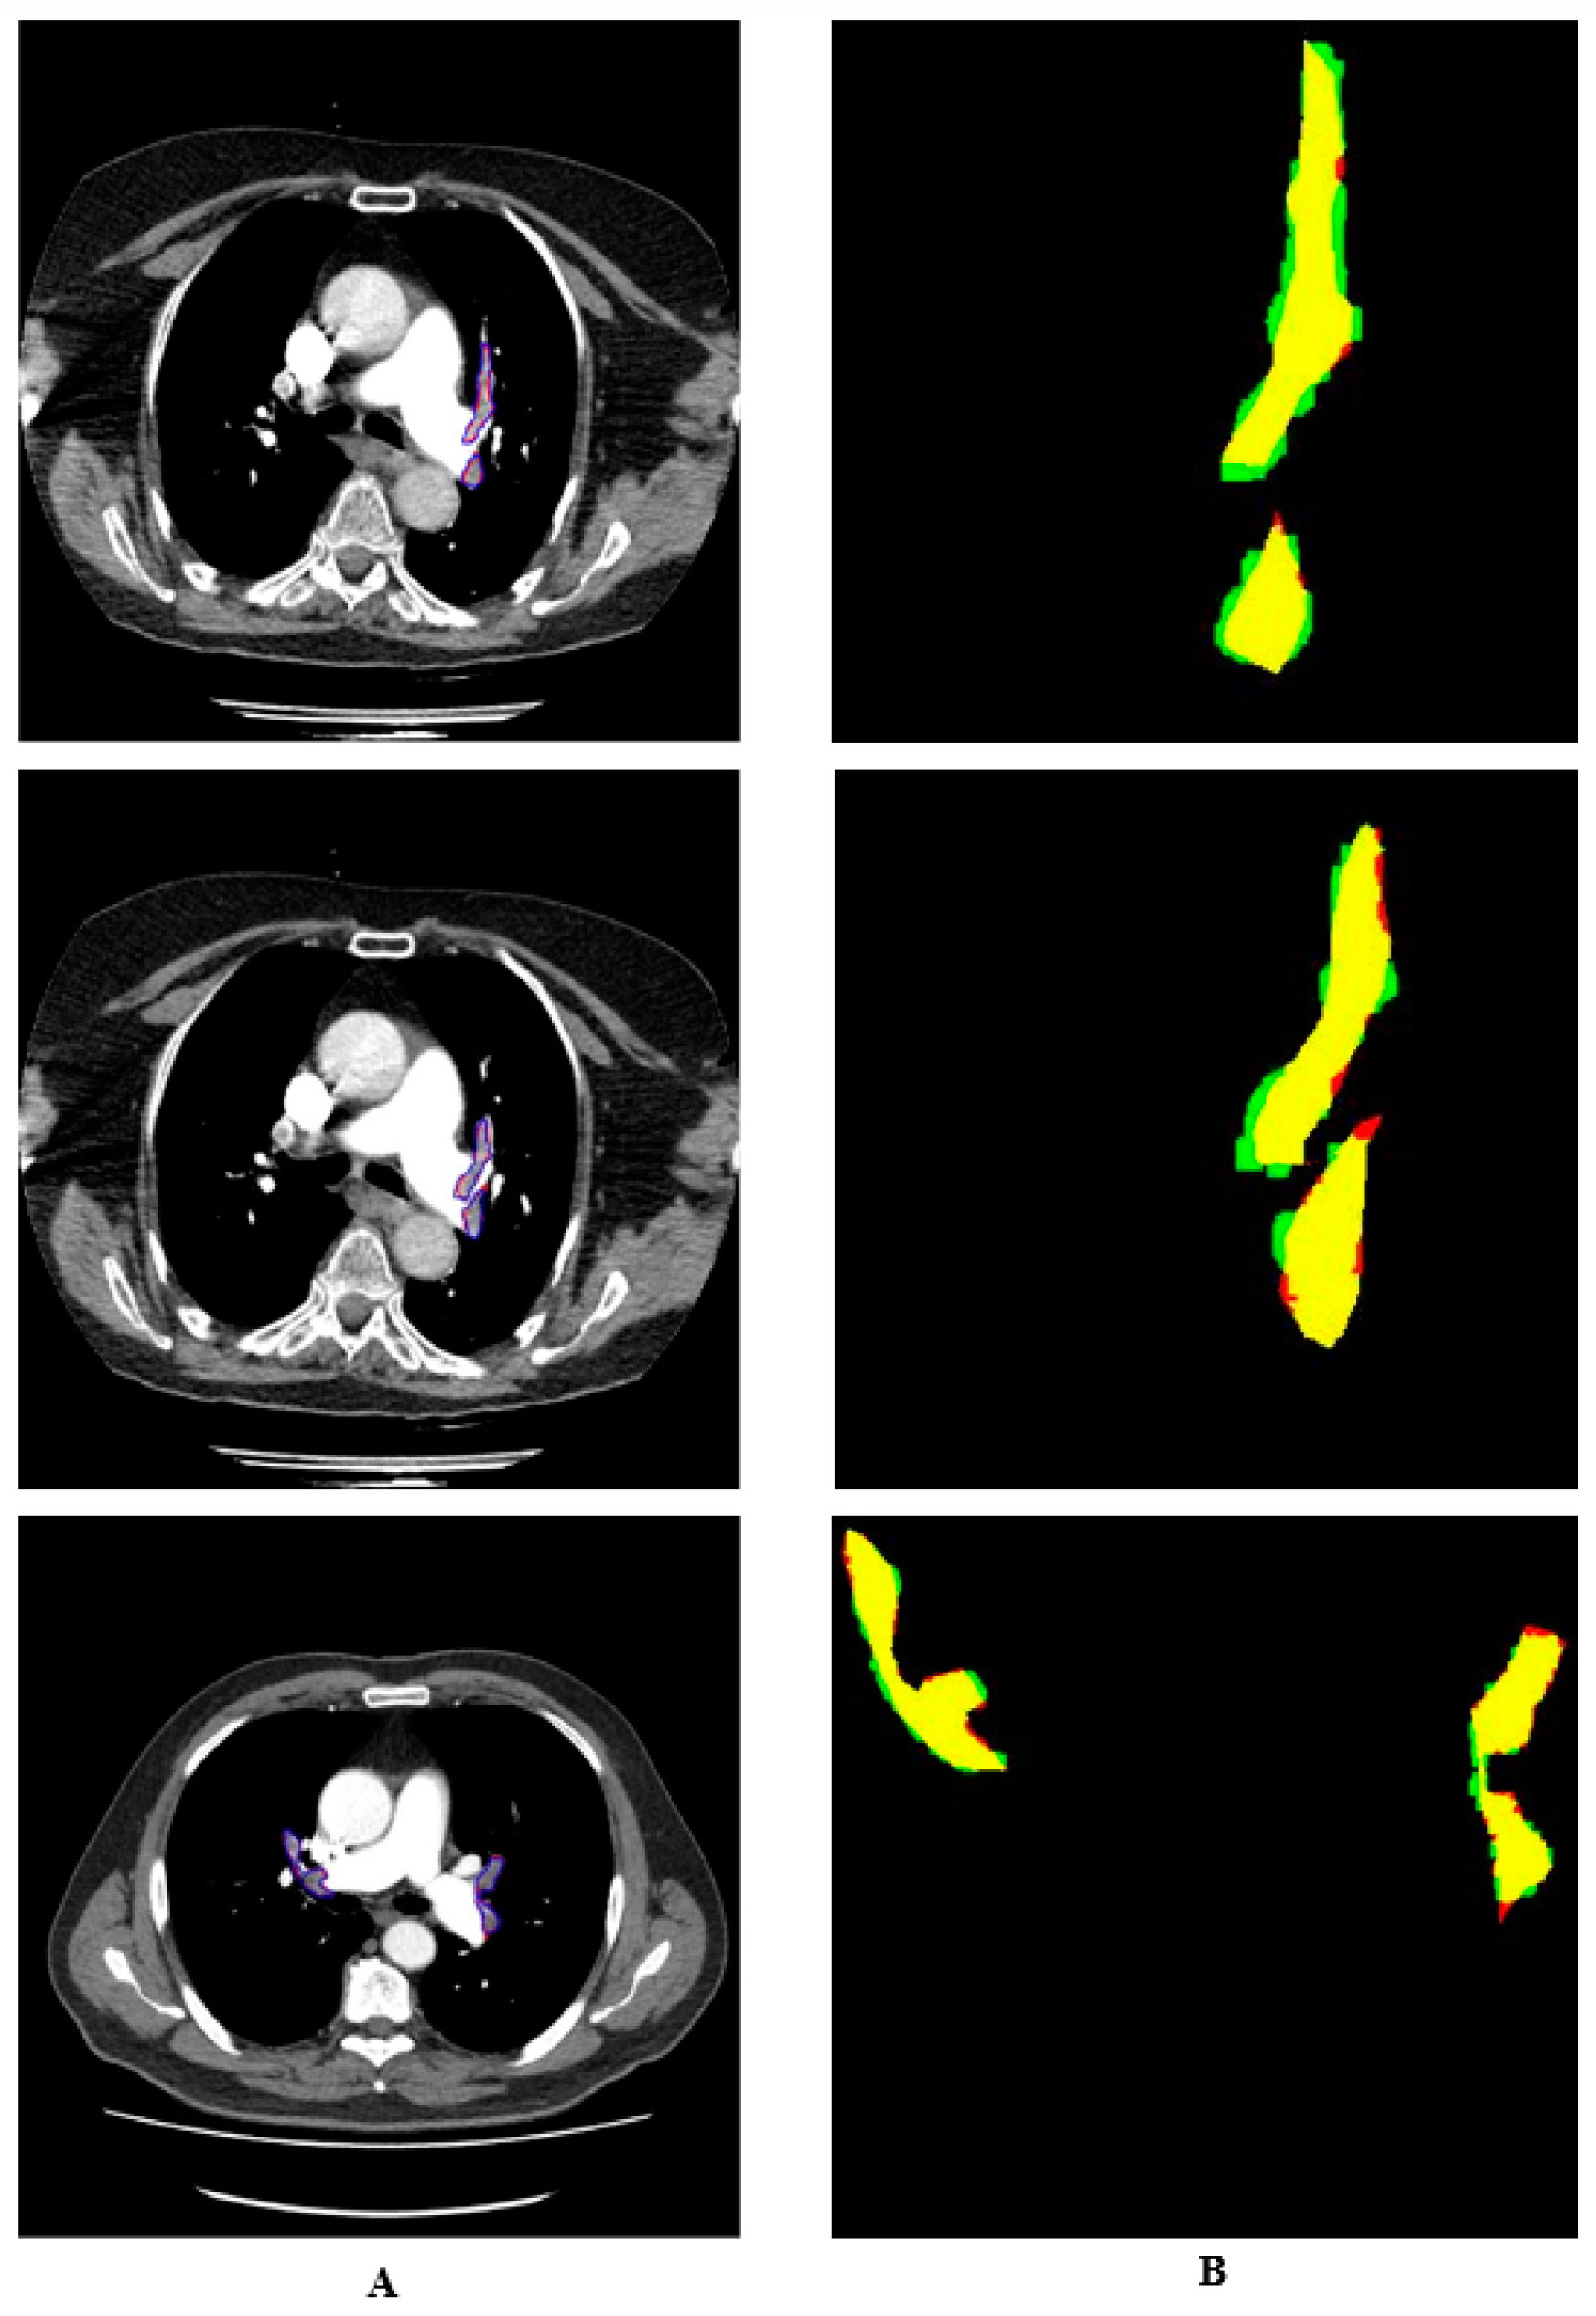

2.4. Enhanced Mask R-CNN Architecture

3. Results and Discussion